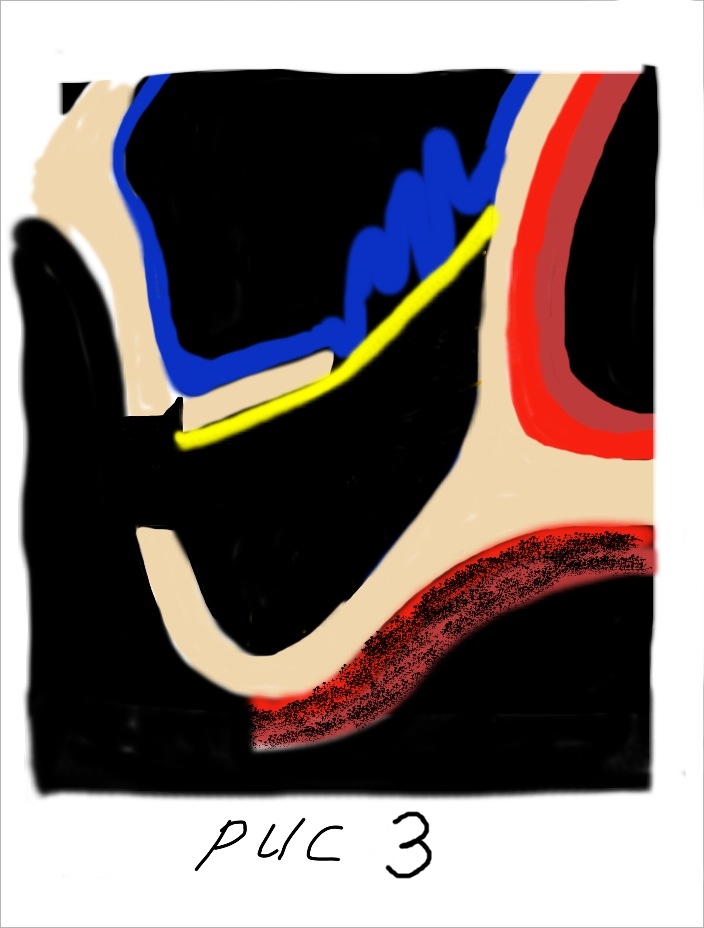

При этом, чем выше мы поднимаем слизистую пазухи тем больше кровоснабжения из соседних участков мы можем получить (рис 2).

При этом, чем выше мы поднимаем слизистую пазухи тем больше кровоснабжения из соседних участков мы можем получить (рис 2).  Сосудистая сеть наружной стенки носа многослойная и обильная. Следовательно, получить кровоснабжение из данного источника очень легко. Для этого необходимо как можно выше отсепарировать слизистую пазухи с носовой стенки. Благодаря этому мы получаем несколько плюсов. Во первых, напряжение слизистой уменьшается она становиться складчатой. Это предупреждает возникновение разрывов и трещин во время аугментации. Во вторых, мы получаем доступ к месту с обильным кровоснабжением которое крайне необходимо для последующего костеобразования и ремоделирования костной ткани.

Сосудистая сеть наружной стенки носа многослойная и обильная. Следовательно, получить кровоснабжение из данного источника очень легко. Для этого необходимо как можно выше отсепарировать слизистую пазухи с носовой стенки. Благодаря этому мы получаем несколько плюсов. Во первых, напряжение слизистой уменьшается она становиться складчатой. Это предупреждает возникновение разрывов и трещин во время аугментации. Во вторых, мы получаем доступ к месту с обильным кровоснабжением которое крайне необходимо для последующего костеобразования и ремоделирования костной ткани.